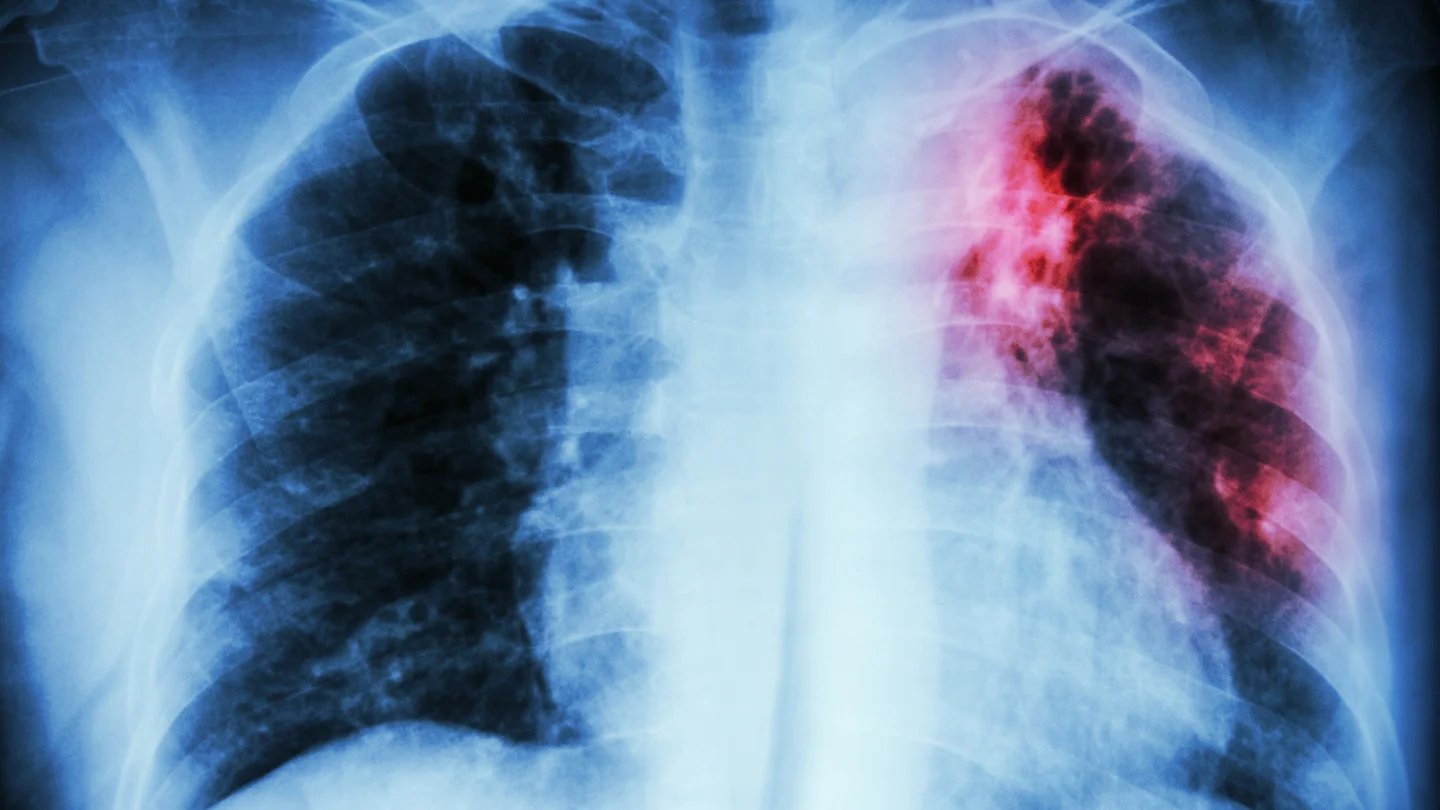

Neben dem Erregernachweis gehört zur Diagnostik immer auch eine Röntgenaufnahme der Lunge. Damit können Ärztinnen und Ärzte feststellen, ob Hinweise auf eine Lungentuberkulose vorliegen, die unter Umständen ansteckend sein kann. Anhand der Röntgenaufnahme kann man auch beurteilen, ob die Behandlung einer Lungentuberkulose erfolgreich verläuft. Um Veränderungen an der Lunge genauer beurteilen zu können, kann in einigen Fällen auch eine Computertomografie durchgeführt werden, ein sogenanntes Schichtröntgen.